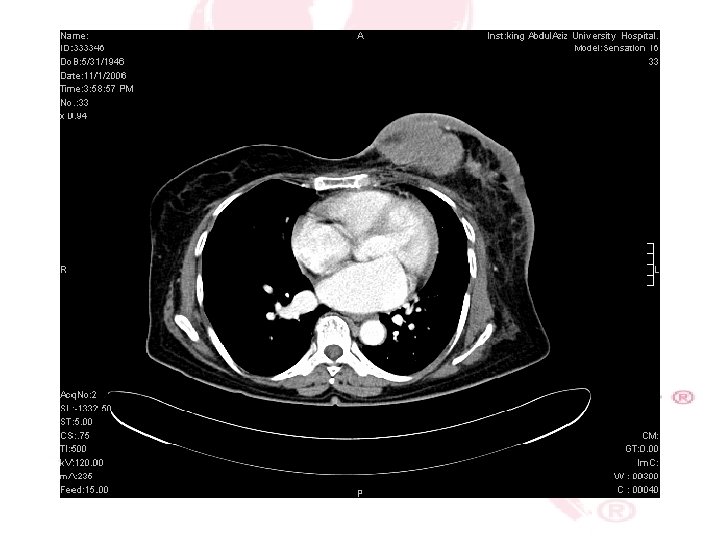

CT SCAN CHEST , ABDOMEN &PELVIS